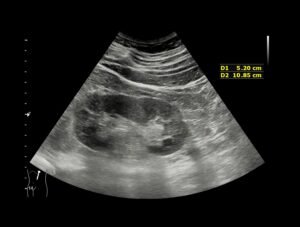

• Ultrasound or other imaging studies to check for structural issues

Ultrasound scan being performed to check bladder and kidneys for causes of recurrent UTIs